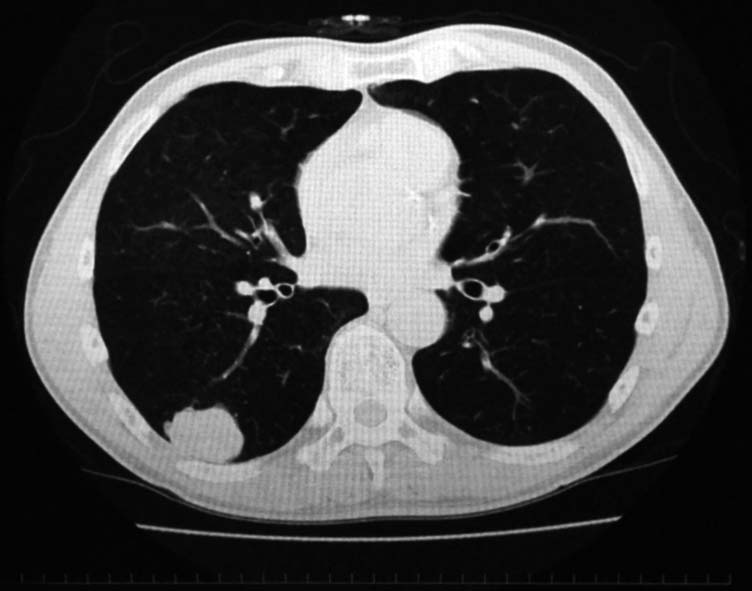

右肺下葉, S6bを主体に一部S9に広がる4.2x3.7x2.5cmの腫瘤. 辺縁凹凸不整, 胸膜に接し内部には不整形の小石灰化がある.肺癌疑い.気管支鏡TBBでは組織片が採取できなかった.

PETで原発巣にSUV max2.2の淡い集積. リンパ節には集積なし. 遠隔転移なし. 肺癌としてはPET集積が淡いが, cT2/1N0M0の肺癌であればstage1B~2Aとなり根治切除可能のためCTガイド下生検が施行された.

右肺下葉切除術がおこなわれた.